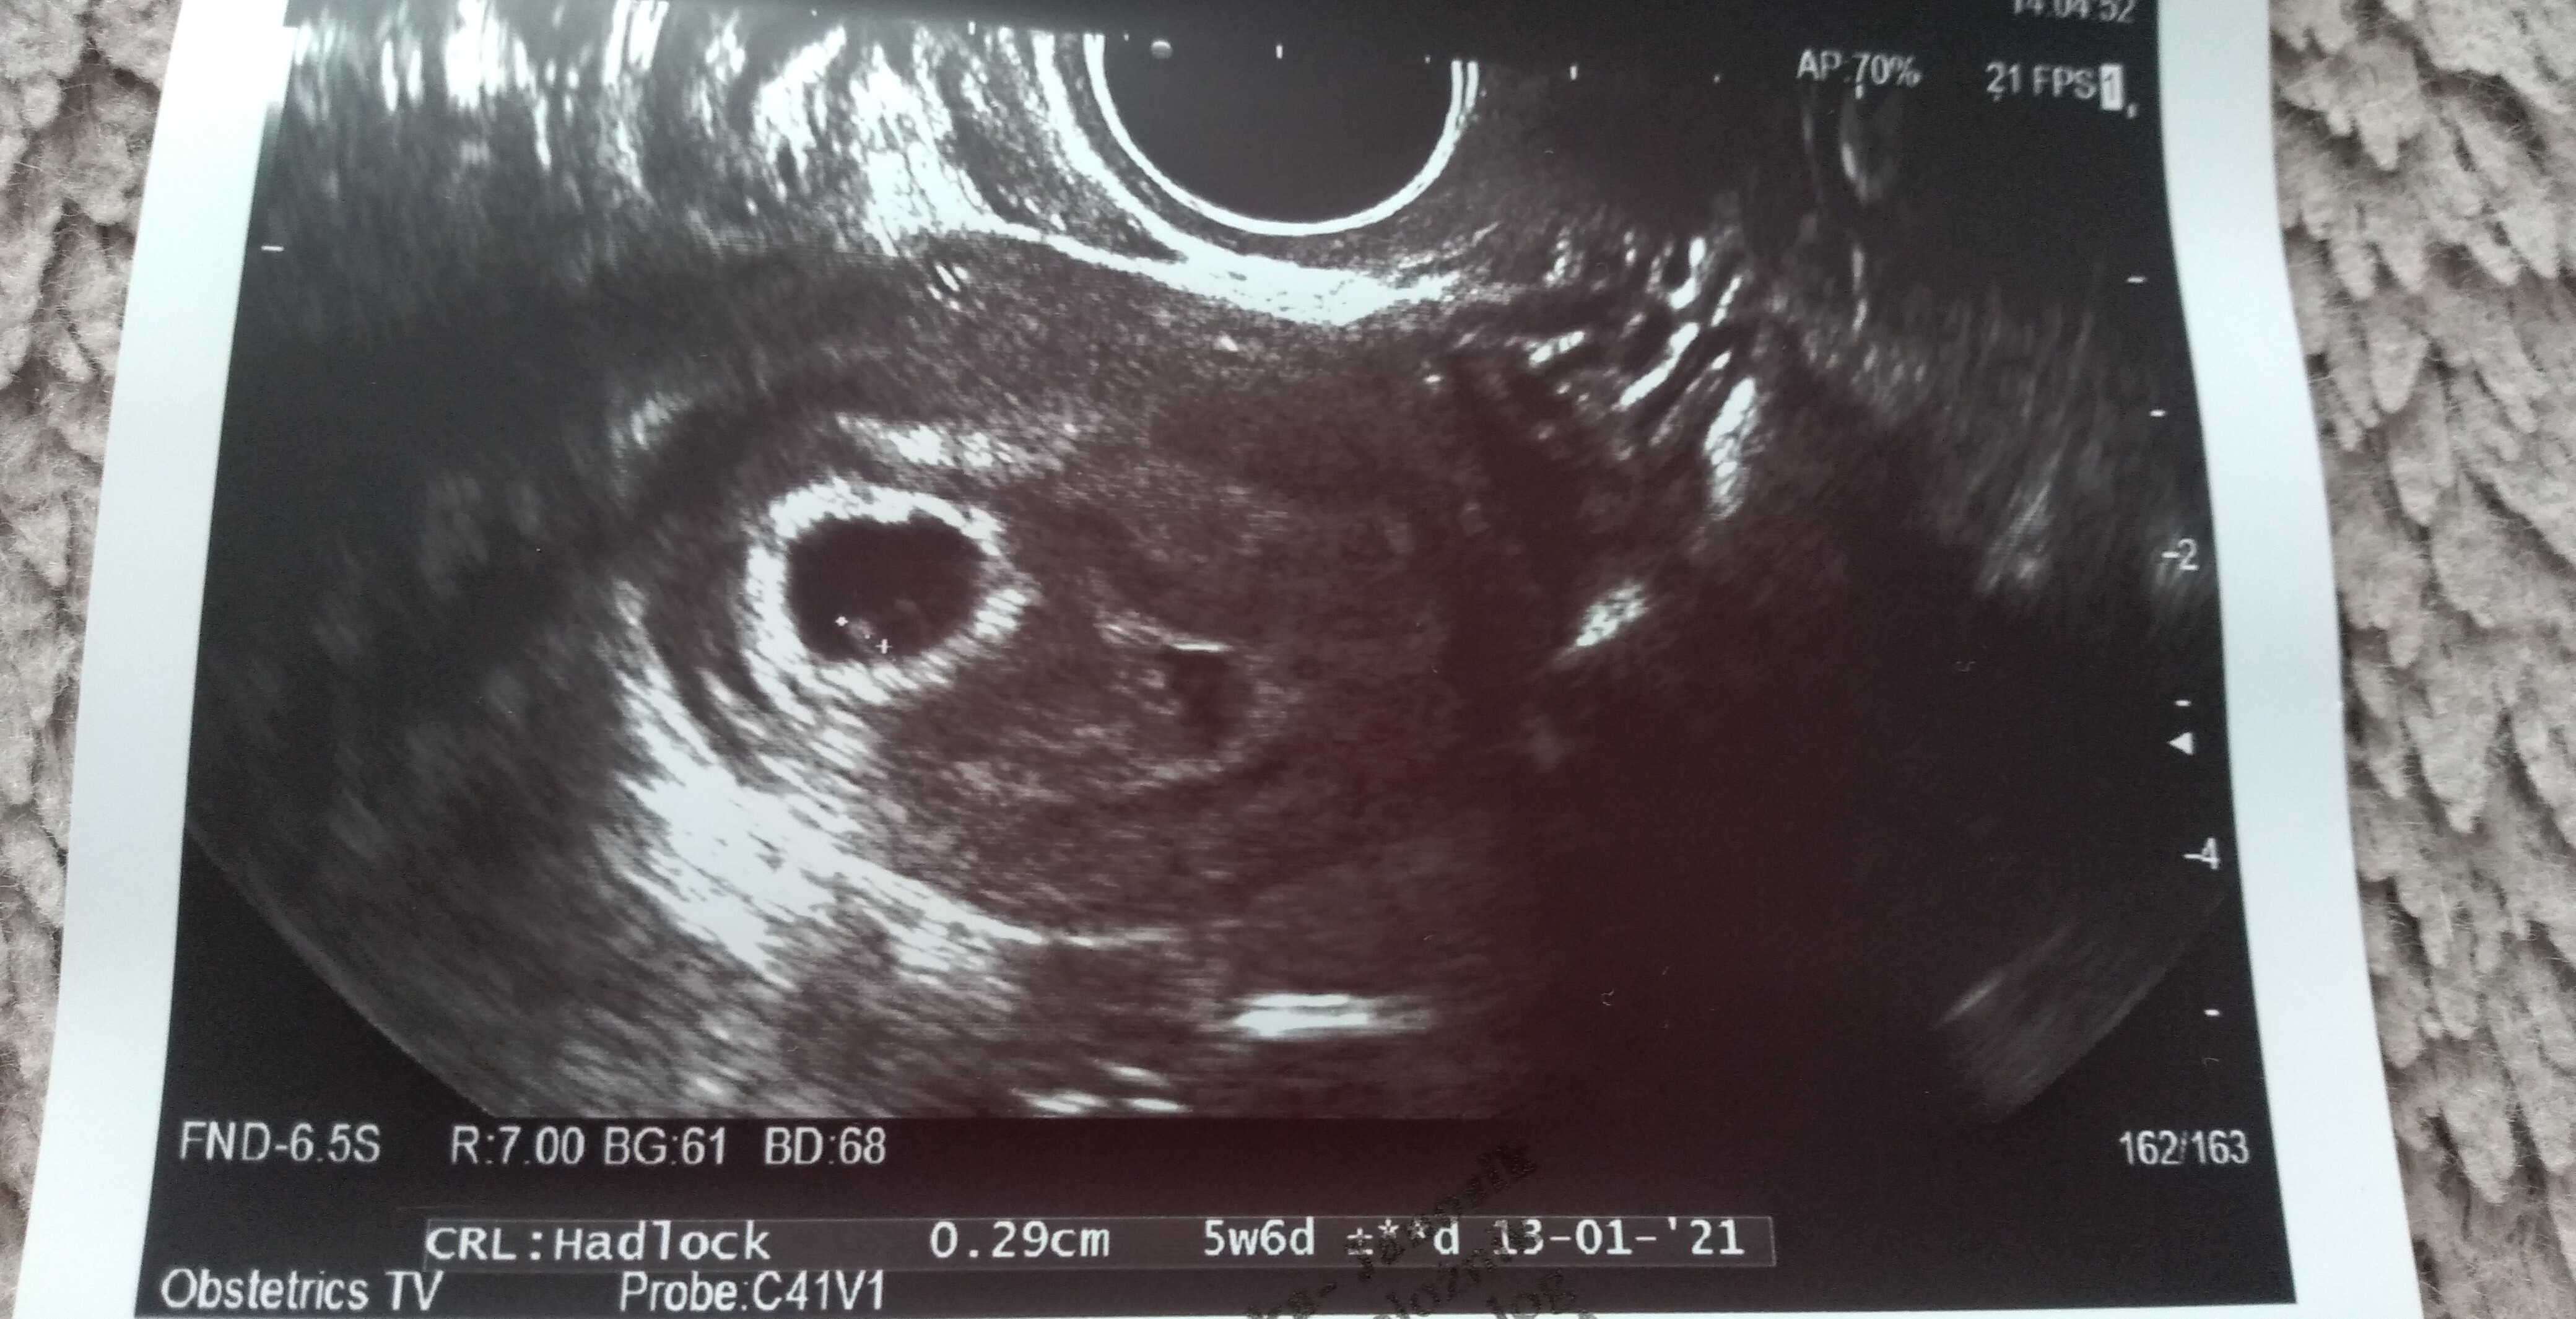

jest zarodek 2,9 mm. Serduszko bije 111/min. Nie puściła mi do słuchania tylko liczyła, widziałam jak faluje.

Dodatkowo mam krwiaka większego dwa razy od pęcherzyka ciążowego - ma 8 na 5 i obok jakieś jeszcze mniejsze...

Różowa strzałka wskazująca to krwiak. Te duże coś na 5 cm to nawet już nie wiem z tego wszystkiego co to było